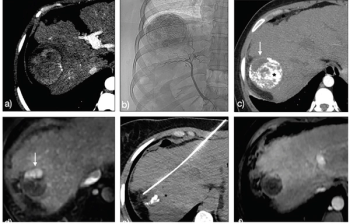

The case of a 64-year-old white woman with hepatitis C virus infection-related well-compensated cirrhosis with hepatocellular carcinoma recuurence.